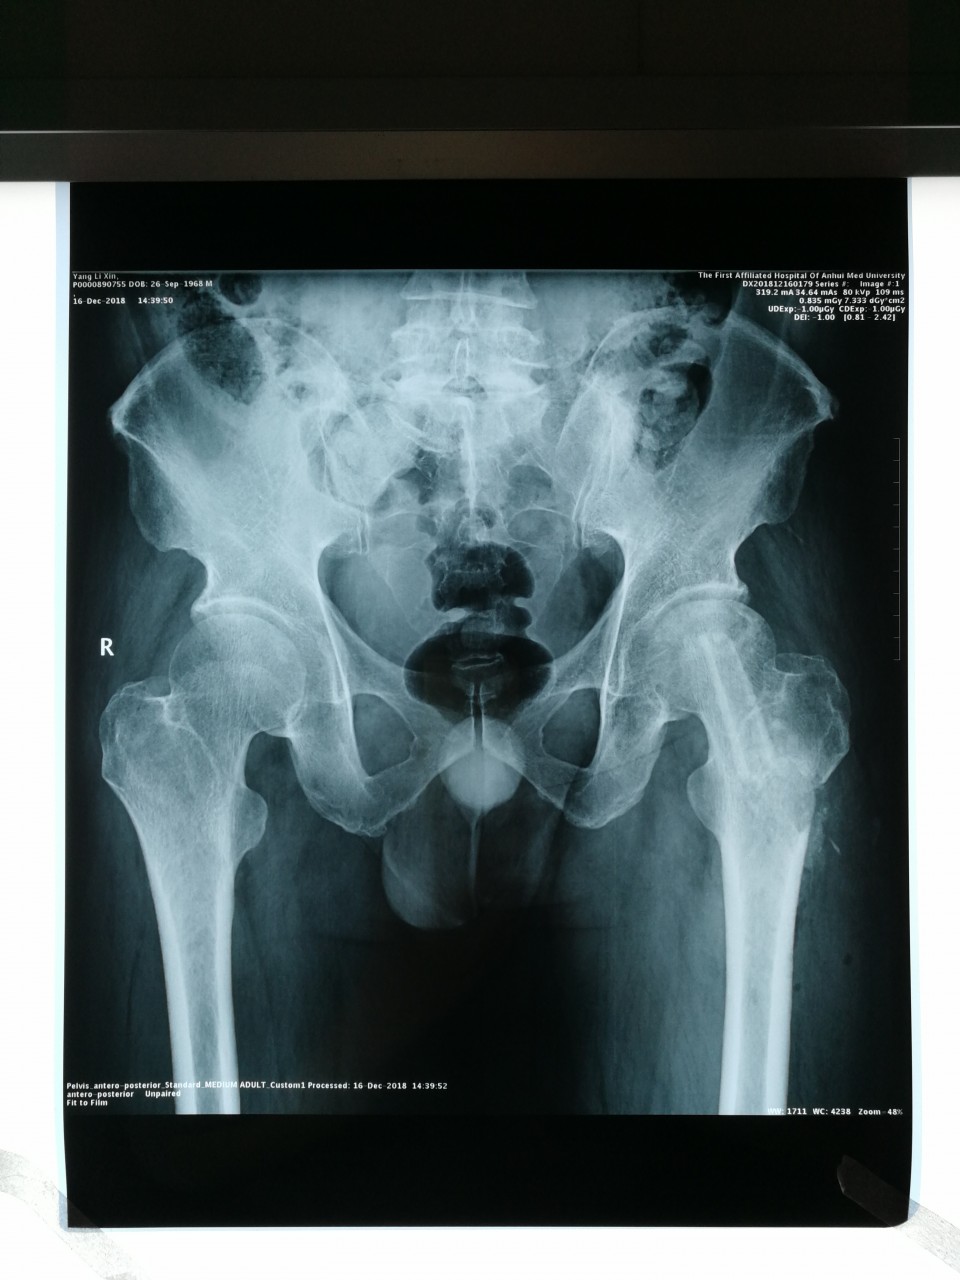

近日,我院创伤骨科病区王刚主任团队利用“天玑”骨科机器人成功为一名股骨头坏死患者施行“机器人导航辅助微创股骨头病灶清除减压+游离腓骨移植术”,患者术后恢复良好,已顺利出院。

股骨头坏死是临床常见疾病之一,常见病因为股骨颈骨折、激素、酗酒等,若早期不进行干预治疗,一旦发生股骨头塌陷,将严重影响行走及日常生活,残疾率高,最终需行髋关节置换术。青壮年早期股骨头坏死的保髋治疗有效率在80%以上,目前国内主流的治疗方法是股骨头病灶清除减压+游离腓骨移植术,但是传统手术手术切口大,病灶定位需要大量射线透视,且不够精确,存在较大局限性。此次创伤骨科王刚主任团队,充分发挥我院“天玑”骨科机器人的优势,利用机器人导航精准定位股骨头坏死中心,再通过小切口进行自体腓骨移植,无需传统内固定辅助,极大地降低了患者费用,减少了术中辐射量。